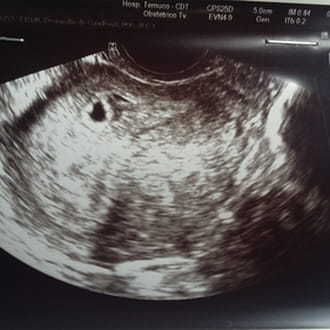

Hola: quisiera ver si me pueden aclarar mi consulta. Estoy embarazada. El primer dia de mi ultima menstruacion fue el.29 de noviembre. Suelen ser cicl...

Hola les cuento tengo 5 semanas de embarazo y me duele mucho la cola y la parte como de los ovarios y ayer tuve un pequeño sangrado y hoy me sale fl...